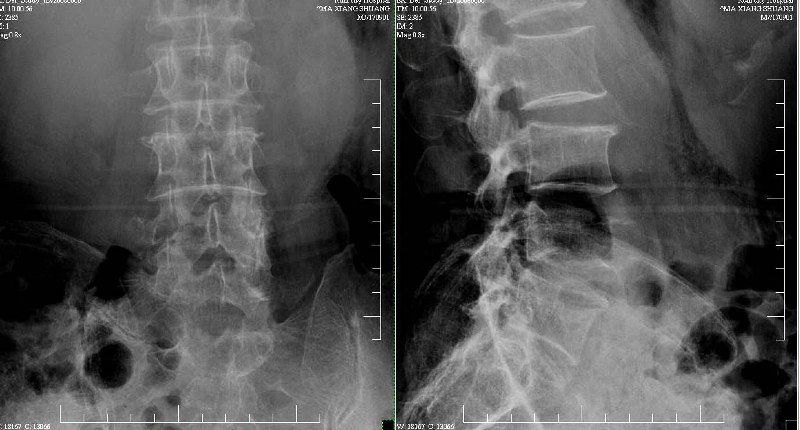

dr:l4骨质破坏,转移可能。

腰椎间盘膨出+突出,椎体考虑为转移、退变。